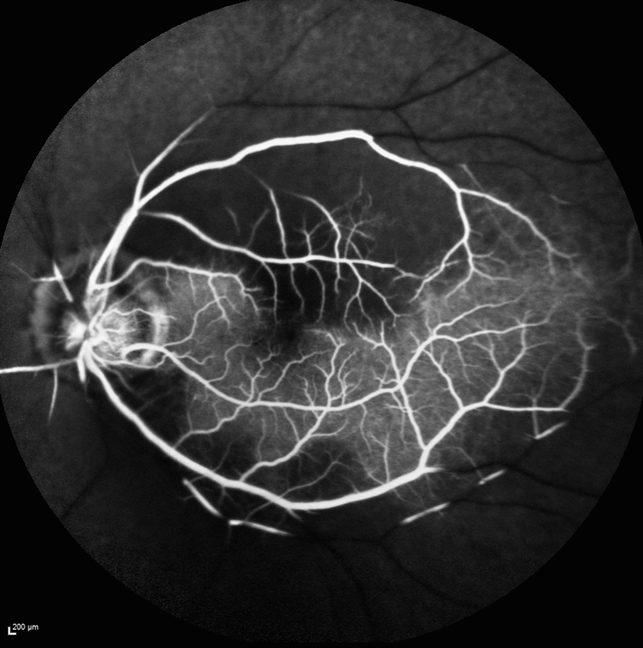

Central Retinal Artery Occlusion with Cilioretinal Sparing Fundus Fluorescein Angiography

Acute Branch Retinal Artery Occlusion and OCT Angiography Imaging

Central retinal artery occlusion (CRAO) is a form of acute ischemic stroke that results in painless vision loss attributable to retinal infarction.. (OCT‐A) to quantify retinal blood flow. OCT‐A uses OCT to differentiate between areas of tissue with erythrocyte movement and nonvascular tissue. 99 However, current OCT‐A.